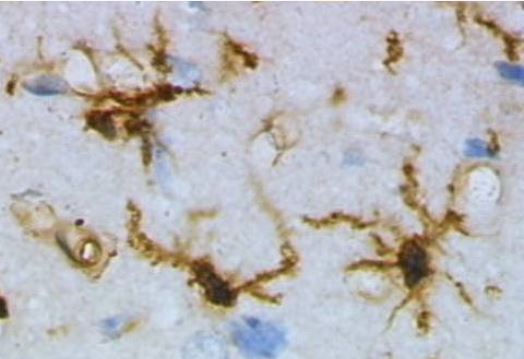

Cèl·lules neuroglials / Foto: Grzegorz Wicher

L'oxidació de la mielina, el recobriment aïllant dels axons de les neurones, pot agreujar les lesions cerebrals a l'esclerosi múltiple en contribuir a l'activació i la disfunció de la micròglia (cèl·lules immunitàries del sistema nerviós). Ho afirma una recerca del grup de Neuroimmunologia de la Universitat de Lleida (UdL) i l'Institut de Recerca Biomèdica de Lleida (IRBLleida), que ha estudiat les respostes cel·lulars sota diferents estats oxidatius. Els resultats, publicats a la revista International Journal of Molecular Sciences, assenyalen que utilitzar cèl·lules induïdes semblants a la micròglia (iMG) permetria avaluar les respostes individuals al dany oxidatiu, obrint la porta a tractaments personalitzats contra la neuroinflamació. [Ampliar notícia]